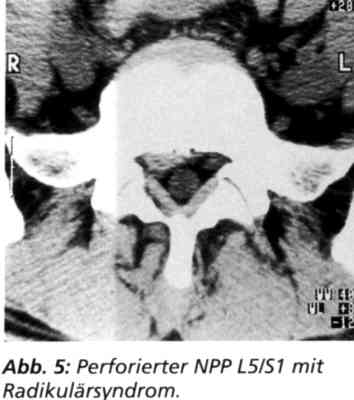

Fall 1: Weibliche Patientin. CT-gesicherter perforierter NPP L5/S1 mit Radikulärsyndrom (Abb. 5). Anamnese: Sechs Wochen Schmerz im Kreuz mit Ausstrahlung ins Bein. Neurologische Zeichen der Sl-Schädigung. Nach der konsequent durchgeführten Sechs-Wochen-Kontrolle postoperativ schmerzfrei, neurologisch ohne Befund, Lasegue von 40 Grad sofort auf 0 postoperativ gebessert. Zwei-Jahres-Kontrolle: Patientin zufrieden, subjektiv beschwerdefrei.